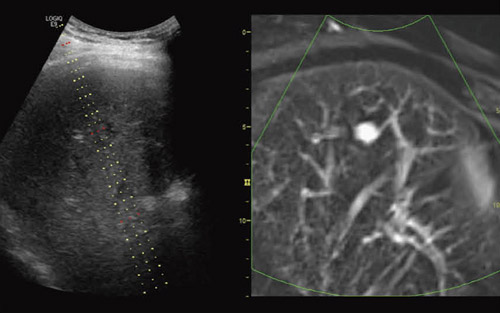

図1にImage Fusionの一例を示す。画面の左側には超音波のリアルタイム画像が表示され,右側には超音波画像の断面位置に対応したCT画像が同期表示され,両者の画像が容易に比較参照できるようになっていることが理解される。参照画像として表示されるCT画像は,あらかじめDICOMで保存されたデータを記録媒体もしくはネットワーク経由で,超音波診断装置上にダウンロードされている必要がある。

図1 超音波とCT,MRIのフュージョン表示

以上の作業により,超音波画像と他モダリティ画像の位置合わせに必要なパラメータが得られる。これ以降は,装置の中で両画像を一致させるための座標変換が自動的に行われ,超音波のリアルタイム画像に追従して,それに対応した他モダリティの断層画像が表示される。位置合わせされた画像は左右に並べて表示したり,一方の画像をカラーコード化し,他方のグレイスケール画像に重畳表示したりすることができる。